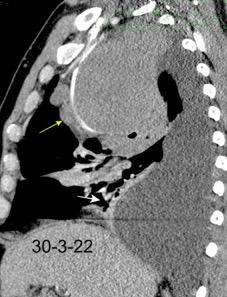

Síndrome de afectación postcardiaca (postcardiac injury)

Post infarto 1-7 % (Dressler)

Trauma cerrado Implantación marcapasos

Cirugía cardiaca. 17-31% (Post.pericardiotomía)

3707 pacientes 29 Derrames (0,78%) > de 25% del hemitórax

Todas menos 2 Izdos.

Angioplastia

By-pass coronario 21-10-03